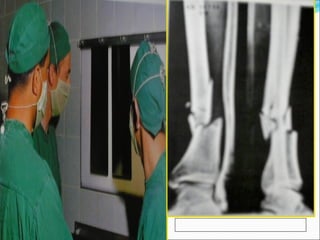

Caso Clínico  Pacientemasculino de 27 anos, golpeado con placa de piedra en pierna izquierda.  Lesión 10X5 cm., en región medial de pierna, con hueso fracciones de hueso visible. LESION GRADO II

Cierre parcial deherida con malla protectora.

Movimiento completo yconsolidación de fractura